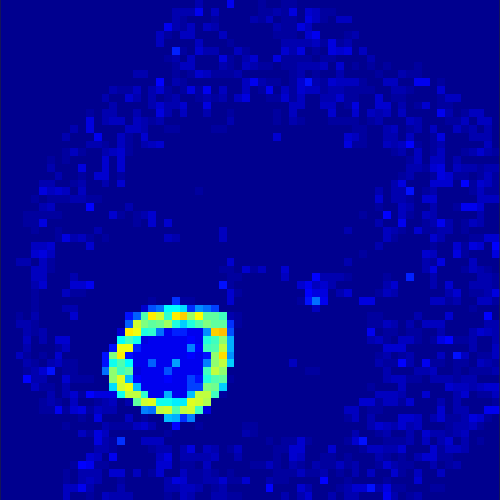

5.2 Monte Carlo Simulation

In order to test the behaviour of the proposed method in a more realistic, random-based test case, we performed a Monte Carlo simulation for dynamic SPECT imaging. First, we created a simple image phantom consisting of an outer and two inner circles which represents the structure of the region of interest (see figure 8(a)). Within those regions we assumed concentration curves over a time period of 90 time steps as displayed in figure 8(b). Based on the tracer intensity in an image frame at each time step, we created a variable number of random decay events (where the number is proportional to the average concentration in one pixel in the whole image frame per time step) with a probability proportional to the concentration in every subregion. They are detected by a virtual double head gamma camera rotating around the patient by 46 degrees per time step, which consists of 374 detector bins. Every simulated decay event is projected onto the scanner and counted by the corresponding detector bin.

In two different tests we fixed the number of events counted by the detector equal to (resp. ) times the average concentration in one pixel. The resulting sinogram images of the accumulated counts in each bin are shown in figure 9.

Based on the sinogram data we applied the proposed algorithm in order to reconstruct the original image sequence. The results for both test cases are shown in figure 10.

As one can see, the method is able to reconstruct the regions properly, even in case of a low count number. Within a number of iterations (average of 100 outer and 10000 inner iterations), the algorithm presents a reasonable reconstruction of the region of interest and the corresponding regional tracer concentration curves. Here, the parameters were not optimized as in the case of the synthesized data sets in the previous section, but kept fixed as , and . With futher optimized parameter values one could possibly provide even better results.